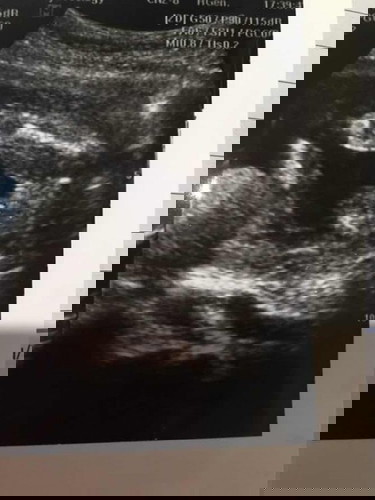

ซาวด์มามะกี้ สดๆร้อนๆป้าหมอบอกผู้หญิงร้อย% สมใจพ่อเขาล่ะ แต่ทำไมแม่เห็นเหมือนผู้ชาย😆 แม่ๆช่วยดูหน่อยค่ะ ญ หรือ ช ท้องแรก 19วีค6วัน ขอบคุณล่วงหน้านะคะ

น้ำหนักแม่ขึ้น2โลเอง ป้าหมอบอกน้ำหนักไปลงที่ลูกหมดเลย😄😄😄